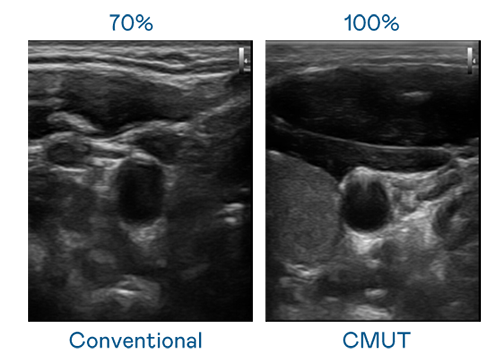

CMUT 技术是一种用电容式微机电元件来产生超音波讯号的技术。与传统 PZT 压电式技术相比,CMUT 频宽增加 30%,更宽频的超音波讯号让影像解析度大幅提升,是实现高影像品质医疗超音波扫描、促进精准医疗发展的关键技术。

大频宽带来超清晰影像

超音波影像的解析度高低,首先取决于探头能发出的讯号频宽。咪鸭直播伴侣 CMUT 可提供高清晰的超音波讯号,提供高频宽、高灵敏度、影像纹理细节更高的超音波影像,协助医护人员缩短影像判读时间及利用精准的医疗影像进行诊断。